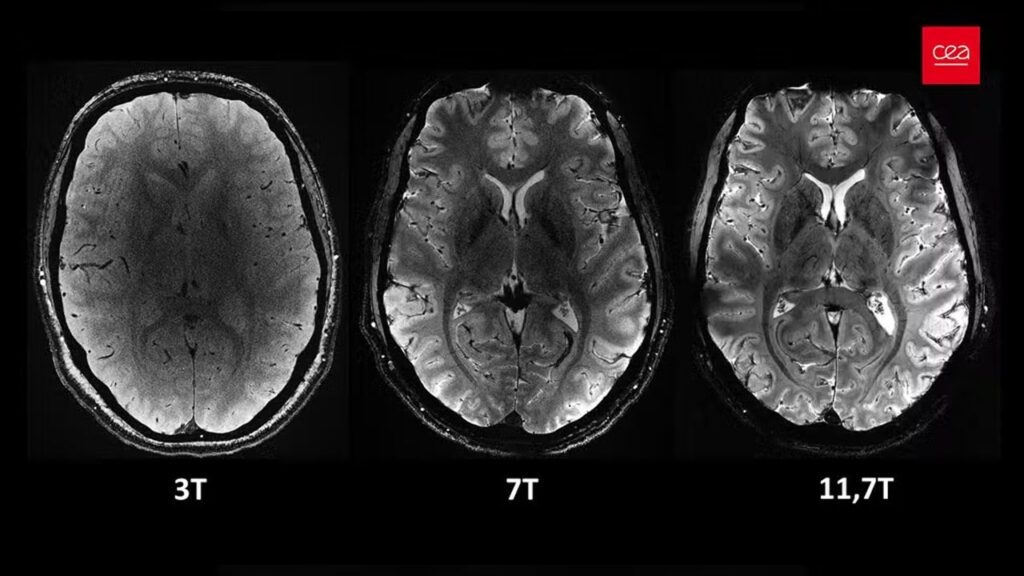

SAÚDE Imagens inéditas do cérebro são reveladas por aparelho de ressonância mais potente do mundo REDAÇÃO 02/04/2024 as 8:16 pm Compartilhe: Quer receber notícias no seu WhatsApp? Então, entre no grupo do Fato360 agora!